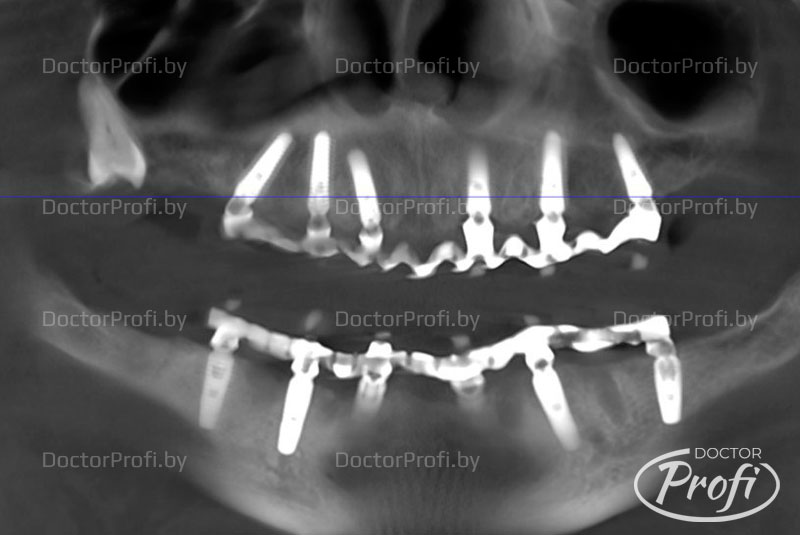

На совместной консультации с ортопедом нами и пациентам было принято решение о проведении имплантации по методике «все-на-6» на верхней и нижней челюсти. Она подразумевает удаление всех зубов, установку шести имплантов на каждой из челюстей и изготовление несъёмной конструкции в течение достаточно короткого периода времени.

Установлено шесть имплантов на нижней челюсти и шесть имплантов на верхней челюсти.